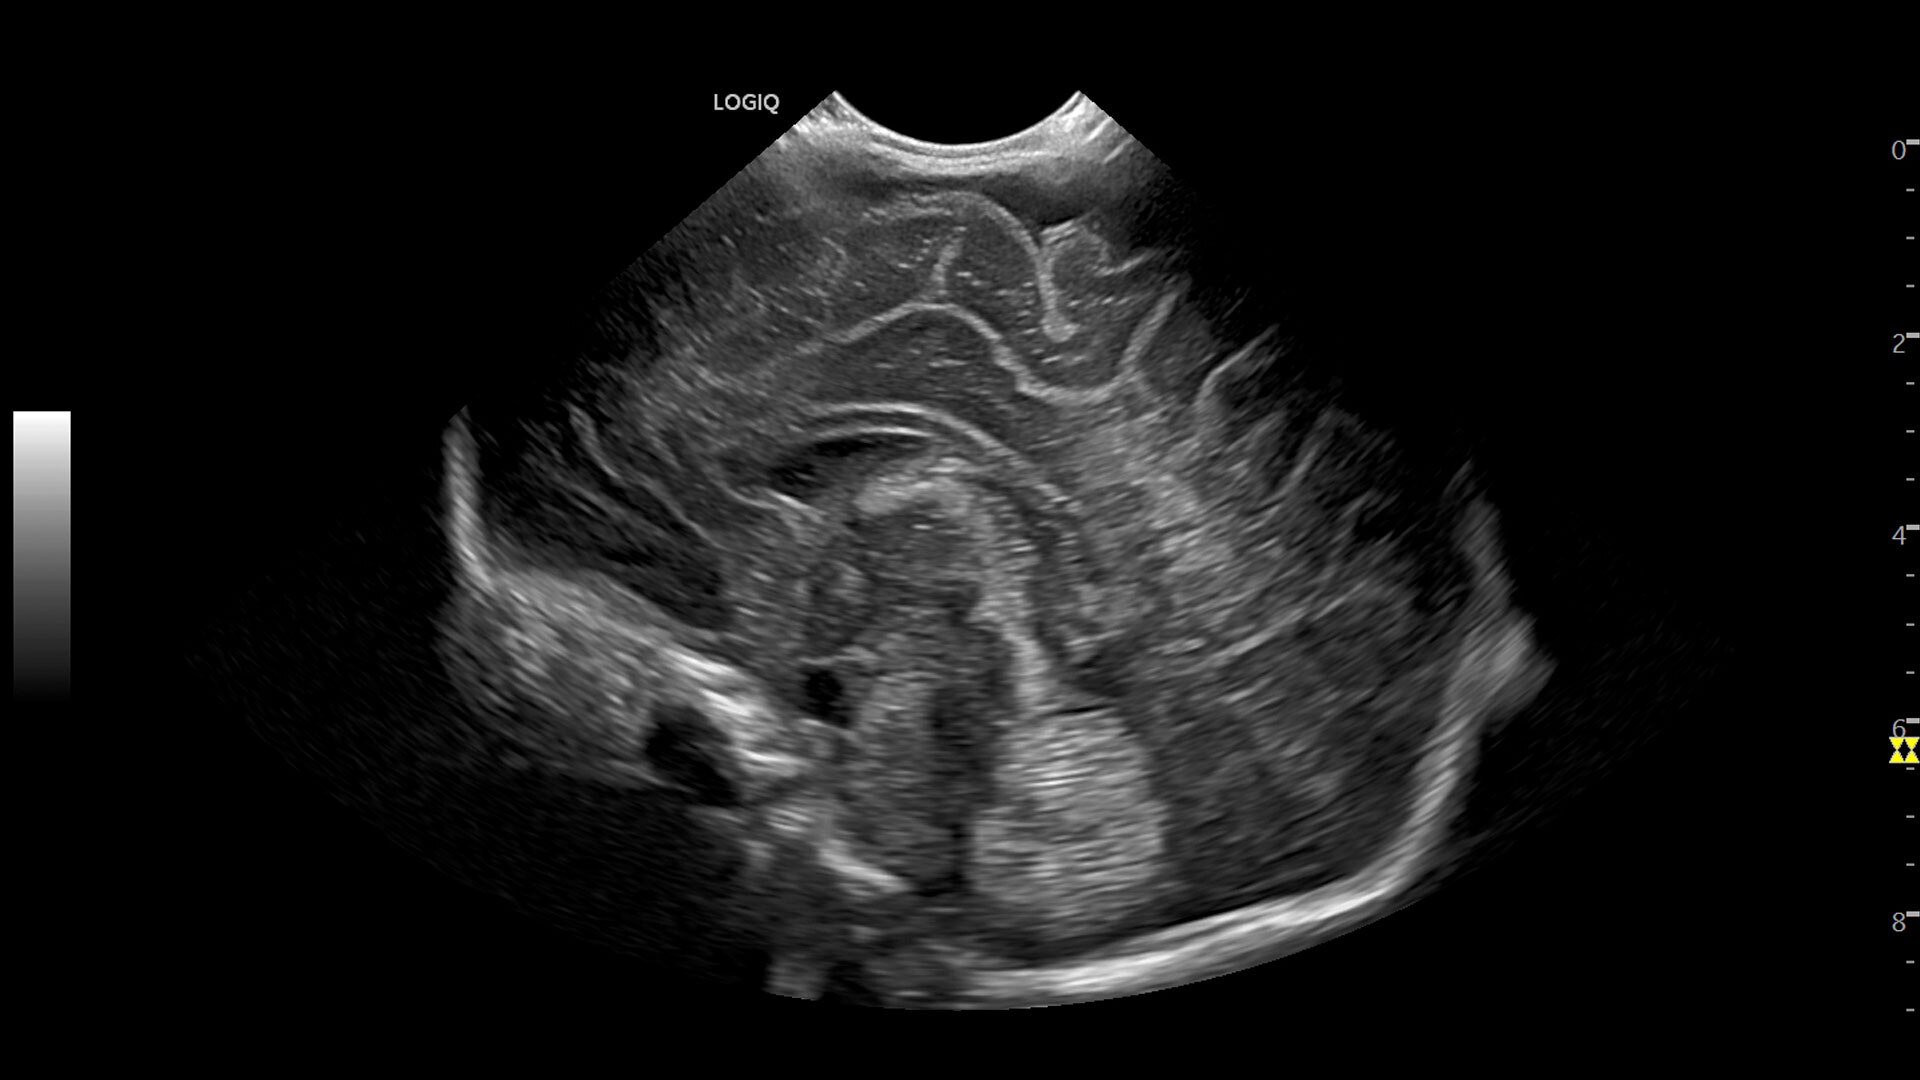

Multi-purpose capabilities, including liver, cardiac, OB/GYN, vascular, breast, thyroid, musculoskeletal, urologic, and pediatric studies.

• 3D/4D with SonoRenderlive